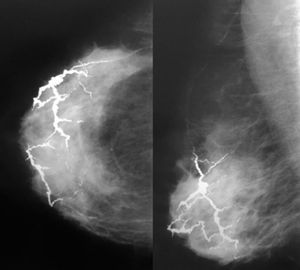

Presentamos una paciente de 55 años con diabetes tipo II e hipertensión, que presentó extensas calcificaciones vasculares que recuerdan a una tormenta eléctrica.

Figura 1 Mamografía en incidencias craneocaudal y oblicua medio lateral de una mama derecha con extensas calcificaciones vasculares.